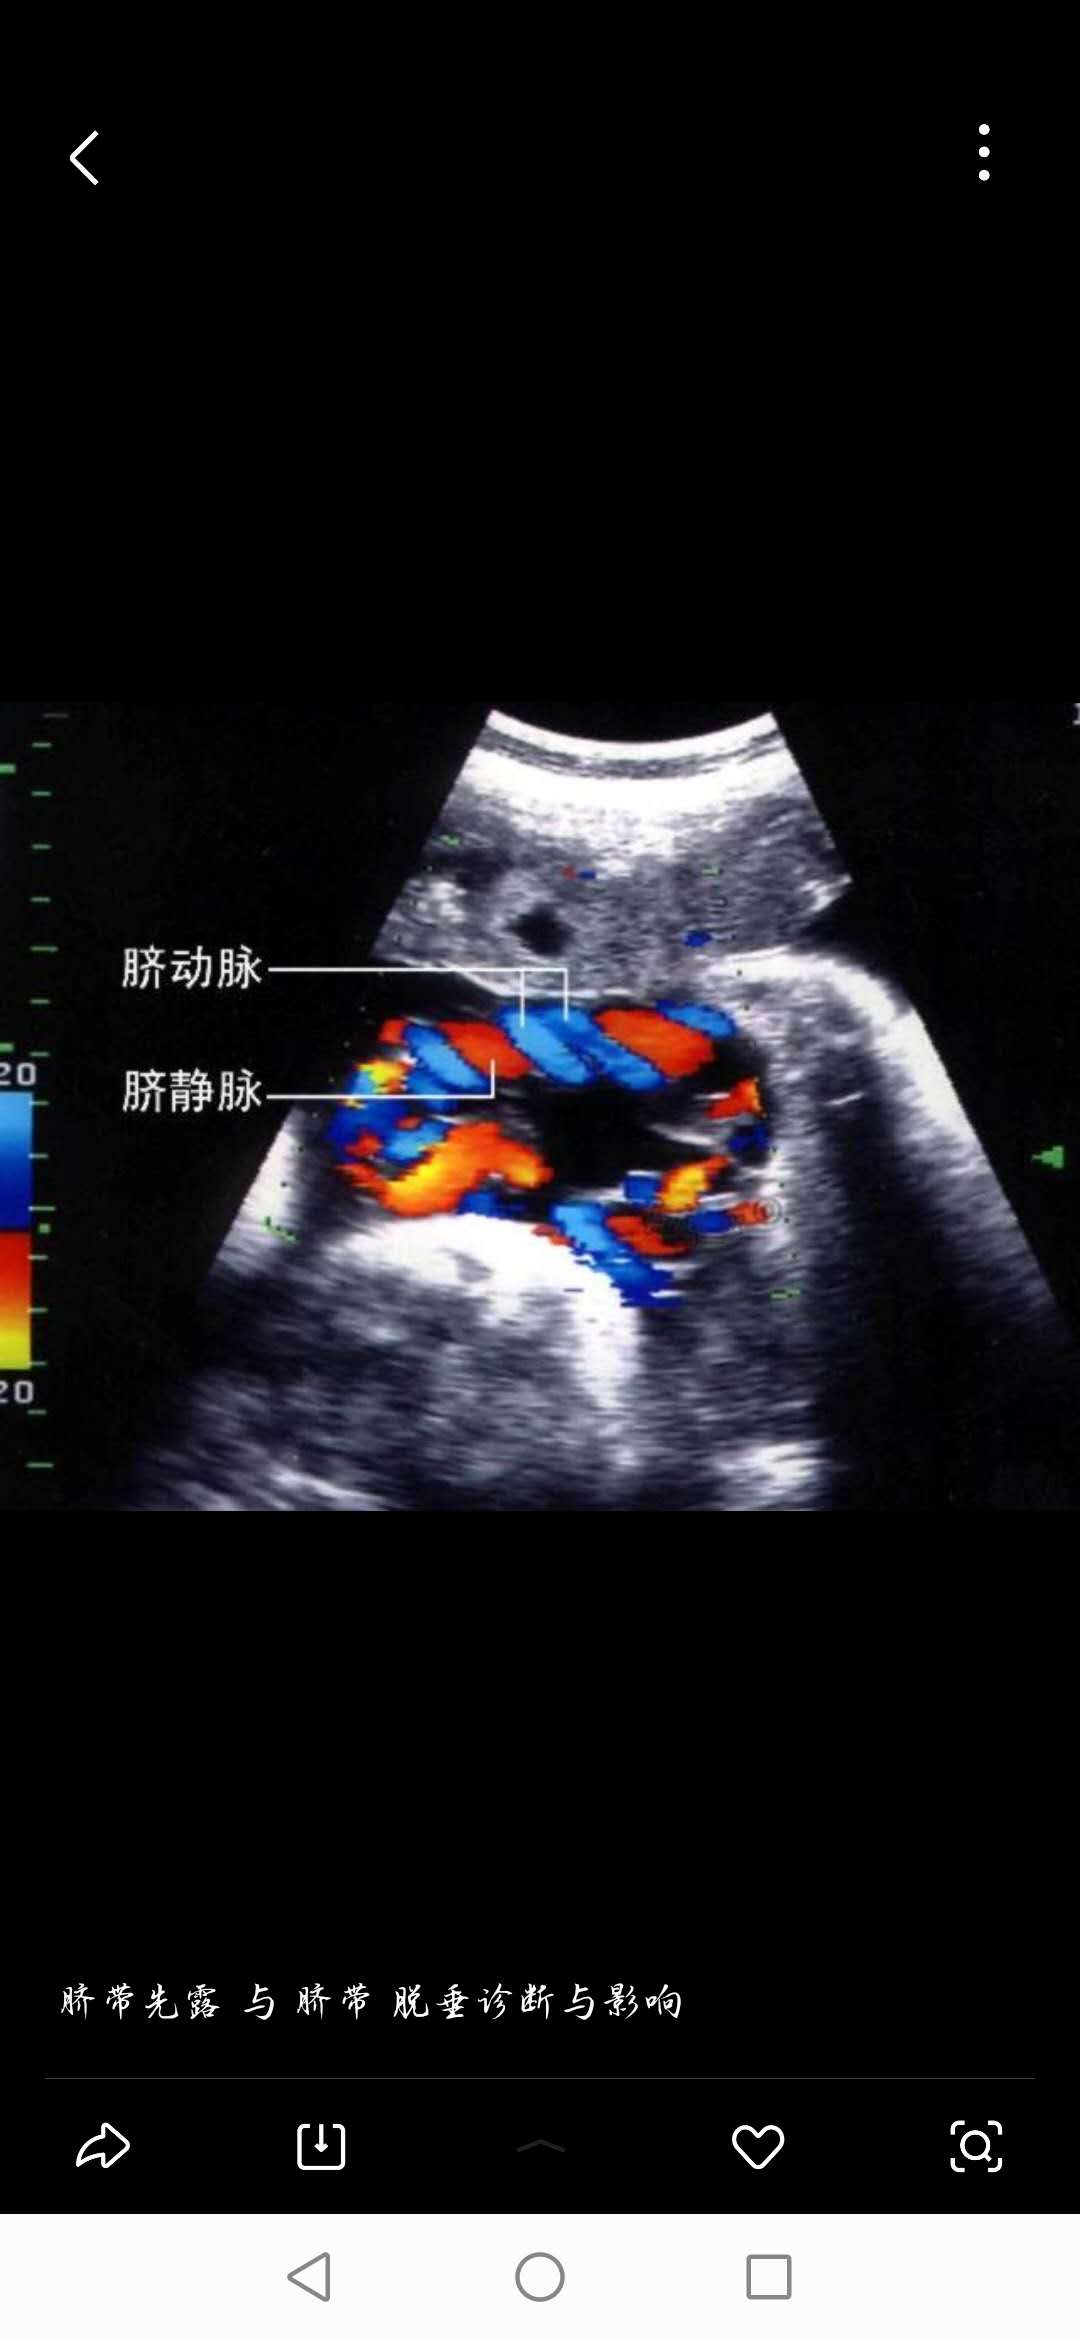

10月21日,一名36周的孕妇,因下腹坠痛来我院检查。产二科主治医师孙中芳接诊后,仔细查体并了解其孕期情况,孕妇31岁,初胎,孕期未规范产检,超声检查:胎头位于耻上,胎头下方宫颈内口上方可见团状脐带回声,提示脐带低于胎头先露部,脐带绕颈一周,同时胎心监护提示20分钟内3次宫缩,宫压明显。存在脐带受压,胎儿宫内窘迫的危险,严重者可能出现胎死宫内。

产二科医务人员争分夺秒紧急救治,对孕妇成功实施了剖宫产术。手术过程中,胎头下方可见一团脐带漂浮,与当时的超声诊断相符。经全体医务人员齐心协作,产妇顺利产下一男婴,重2900克,母子平安。

脐带先露常见于臀位,头位少见,头位合并脐带先露、脐带脱垂者则危险系数显著增加,因胎儿颅骨和产妇骨盆均为骨性成分,当胎头下降后,脐带极容易受压。一旦发生在头位的脐带先露,情况会更严重,若脐带受压、血运完全阻断时间超过8分钟,则极易发生胎死宫内,是产科急症之急症,分秒必争!